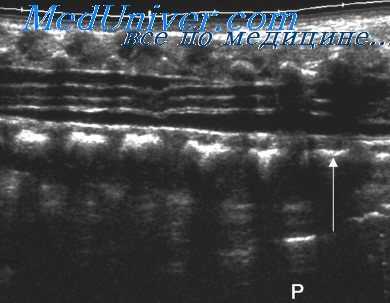

Роль эхографии в диагностике скелетных дисплазии. Имеется множество работ, посвященных роли ультразвукового исследования в диагностике скелетных дисплазии. А.В. Kurtz et al. провели проспективный анализ 16 наблюдений у 15 пациенток из группы высокого генетического риска в отношении развития этих заболеваний. На основании данных, полученных с помощью эхографии во втором триместре беременности, им удалось выявить патологию у 5 из 16 плодов.

По результатам В.М. Weldner et al., обследовавших 12 453 беременных во втором и третьем триместрах, ожидаемая частота распространенности скелетных дисплазии составила 7,5 на 10 000 родов. R. Sarony et al. провели оценку роли пренатальной диагностики на основании данных, полученных при обследовании новорожденных и аутопсии плодов, которые направлялись в их центр из других медицинских учреждений с диагнозом подозрение на скелетную дисплазиюв.

Большинство случаев имело спорадический характер и наиболее частыми окончательными диагнозами были несовершенный остеогенез (16%) и танатофорная дисплазия (14%). G. Gaffney et al. сообщили о 35 наблюдениях с подозрением на скелетную дисплазию. Используя систематический подход при проведении ультразвуковых исследований во втором и третьем триместрах беременности, удалось правильно предсказать исходы в 91% случаев, однако точный диагноз был установлен лишь в 31% наблюдений.

При обследовании за 10 лет большой группы из 12 200 пациенток с высоким риском в отношении развития скелетных дисплазии в сроки беременности от 9 до 40 нед, было обнаружено 39 случаев этой патологии. Из них 30 (76,9%) было диагностировано в первом и втором триместрах. А.Е. Tretter et al. идентифицировали 26 из 27 случаев с летальными формами скелетных аномалий, a J.H. Hersh et al. в 23 наблюдениях из 27 правильно предсказали летальность выявленных аномалий.